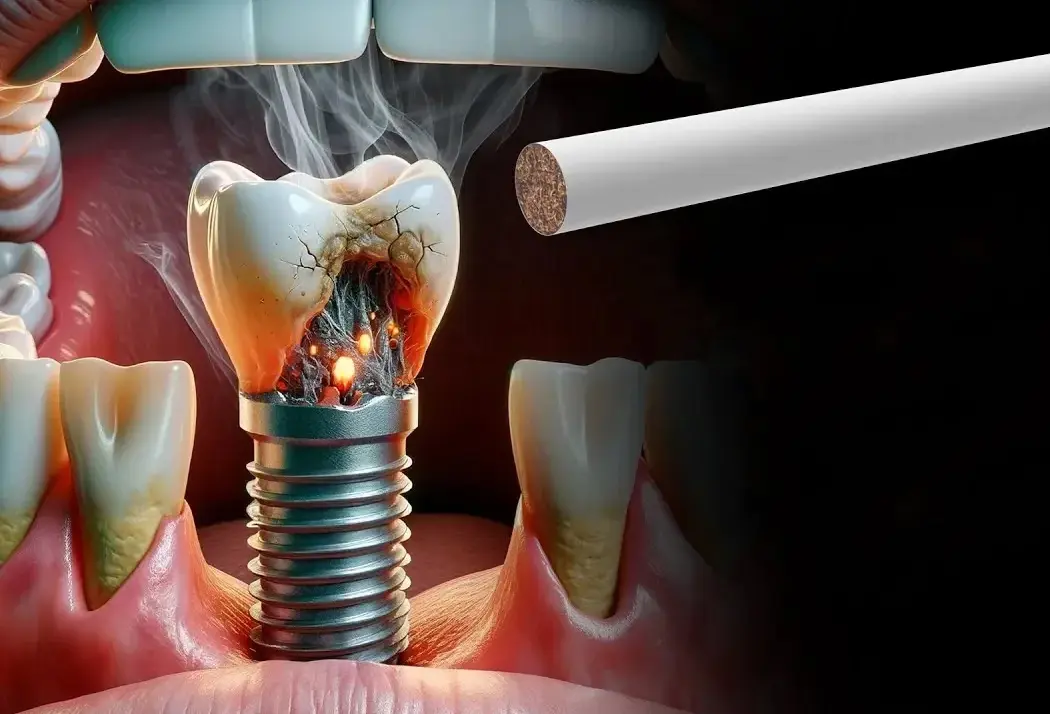

ایمپلنت دندان مصنوعی یکی از روشهای پیشرفته جایگزینی دندان از دست رفته است که با کاشت پایه تیتانیومی در استخوان فک انجام میشود. این روش به دلیل استحکام بالا و شباهت ظاهری و عملکردی به دندان طبیعی، محبوبیت زیادی پیدا کرده است. در فرآیند نصب، ابتدا پایه در فک قرار گرفته و سپس تاج دندان روی آن سوار میشود. استفاده از ایمپلنت دندان باعث میشود بیمار بتواند دوباره با اعتماد به نفس لبخند بزند. برخلاف دندان مصنوعی متحرک، این روش ثابت و ماندگار است که سبب میشود بسیاری از افراد، این روش را به مدل سنتی ترجیح بدهند. کیفیت ساخت و متریال به کار رفته در ایمپلنت دندان مصنوعی نقش مهمی در طول عمر آن دارد. البته نکتهای که باید به آن توجه کنید این است که مراقبت صحیح از آن همانند دندان طبیعی اهمیت بالایی دارد.

در انتخاب ایمپلنت دندان مصنوعی باید به شرایط فک، تراکم استخوان و وضعیت لثهها توجه شود. افرادی که دچار تحلیل استخوان فک هستند، ممکن است نیاز به جراحیهای تکمیلی داشته باشند. استفاده از فناوریهای نوین مانند ایمپلنت دندان دیجیتالی باعث افزایش دقت و کاهش زمان جراحی شده است. پزشکان با اسکن سه بعدی دهان، طرح دقیق کاشت را آماده میکنند. ایمپلنت دندان در این حالت نه تنها ظاهری طبیعی دارد بلکه عملکرد جویدن را نیز بهبود میبخشد. باید خاطرنشان کنیم که رعایت بهداشت دهان پس از جراحی ضروری است. همچنین انتخاب یک کلینیک معتبر میتواند تاثیر زیادی بر موفقیت درمان داشته باشد. مراقبت منظم و مراجعه به دندانپزشک نکته ضروری و مهم دیگری است که نباید از آن غافل شوید.

ایمپلنت دندان مصنوعی نه تنها جنبه زیبایی دارد، بلکه از نظر حفظ سلامت فک نیز اهمیت بالایی دارد. وقتی دندان از دست میرود، استخوان فک به مرور تحلیل رفته و ساختار صورت تغییر میکند. با کاشت ایمپلنت دندان، این روند متوقف میشود. در این روش، تکیه گاه دندان جدید مستقیماً با استخوان پیوند میخورد. این اتصال محکم باعث میشود بیمار بتواند با اطمینان غذاهای سفت را نیز بجود. افرادی که از دندان مصنوعی متحرک ناراضی هستند، معمولاً از ایمپلنت استقبال میکنند و رضایت بالای این روش گواهی برای تایید این مسئله محسوب میشود.

برای پاسخ به پرسش ایمپلنت دندان مصنوعی چیست باید گفت این یک روش پیشرفته دندانپزشکی است که جایگزین دندانهای از دست رفته میشود. در این روش پایهای فلزی، معمولاً از جنس تیتانیوم، در استخوان فک قرار داده میشود تا نقش ریشه دندان را ایفا کند. سپس تاج یا پروتز دندان روی این پایه نصب میشود. ایمپلنت دندان مصنوعی به دلیل ثبات بالا و شباهت به دندان طبیعی، هم از نظر زیبایی و هم عملکرد مورد توجه و استقبال طیف گستردهای از بیماران قرار گرفته است. این درمان با مراقبت صحیح میتواند سالها دوام داشته باشد. همچنین، انتخاب پزشک باتجربه اهمیت زیادی در موفقیت آن دارد.

وقتی میخواهیم بدانیم ایمپلنت دندان مصنوعی چیست، باید به جنبههای عملکردی آن نیز توجه کنیم. این روش باعث میشود بیمار بتواند بدون نگرانی از افتادن یا لق شدن دندان، به راحتی غذا بخورد و صحبت کند. ایمپلنت دندان مصنوعی فشار جویدن را به طور مستقیم به استخوان منتقل میکند و این امر مانع تحلیل فک میشود. برخلاف پروتزهای متحرک که نیاز به چسب ایمپلنت دندان دارند، این روش کاملاً ثابت است. فرآیند کاشت شامل مراحل آماده سازی فک، کاشت پایه و نصب تاج است. ماندگاری بالای این روش، آن را به یک انتخاب محبوب تبدیل کرده است.